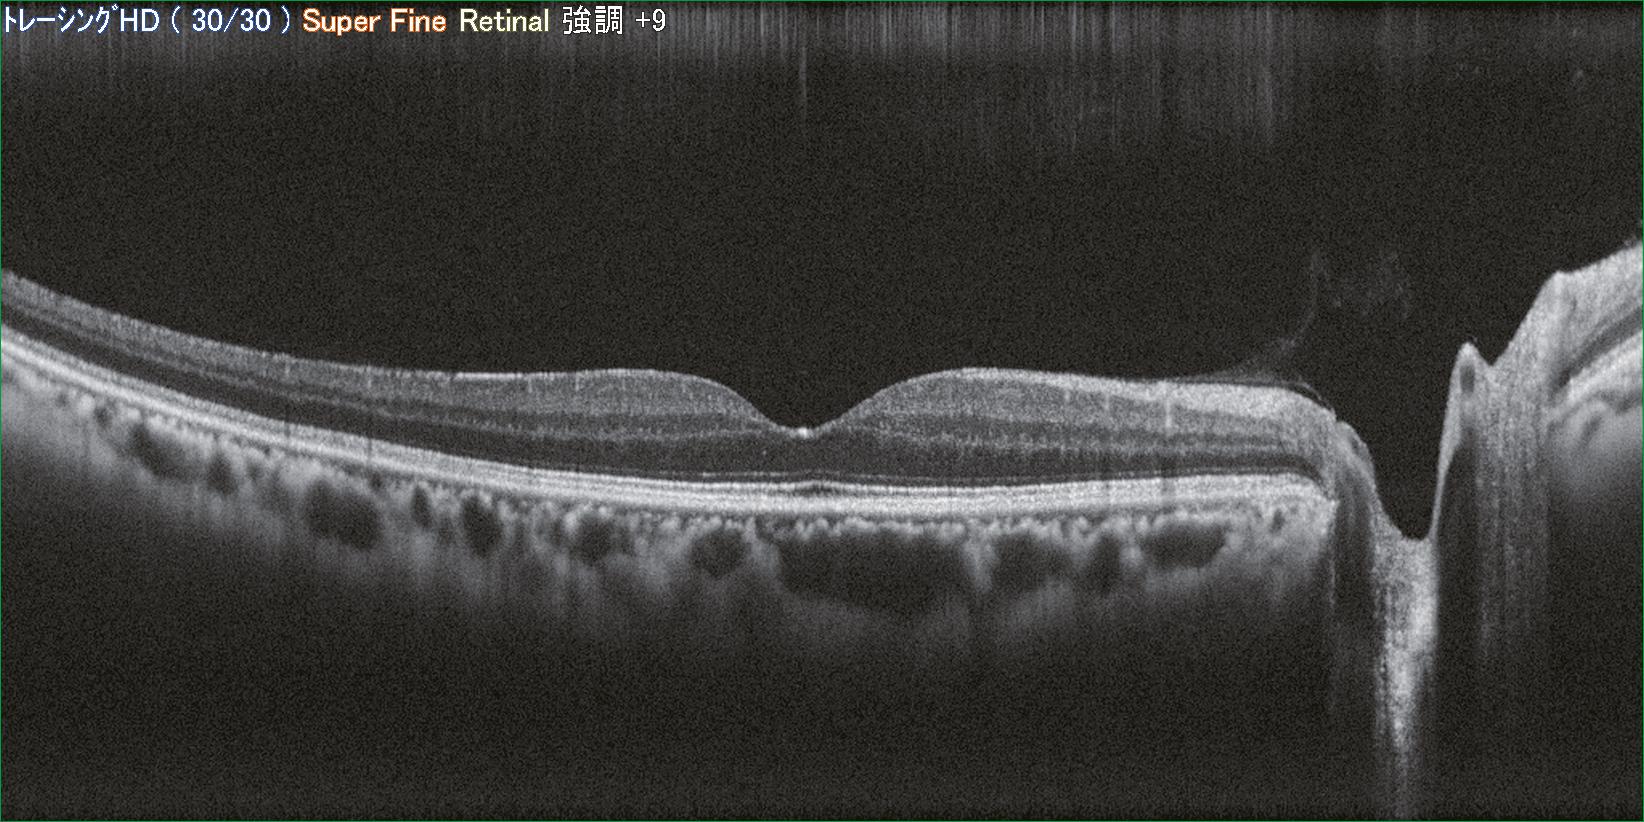

Pour une utilisation conviviale, l’appareil suit l’œil du patient en temps réel et réalise l’alignement sur la pupille, la mise au point sur la rétine et le déclenchement de l’acquisition (OCT + photo). Avec son nouveau scan Retina Map, combinant analyse maculaire et papillaire en une seule prise, le Retina Scan Duo 2 est parfaitement adapté à une utilisation de routine destiné au dépistage et la standardisation des examens. La modification de la sensibilité du signal (mode Regular, Fine ou Ultra-Fine) est un paramètre modifiable renforçant l’intensité du signal lors d’opacité des milieux.

Pour une expertise plus poussée, d’autres modalités d’imagerie sont également possibles, plusieurs coupes OCT sont disponibles ainsi qu’une sommation des images jusqu’à 50 coupes (mode HD), un mode EDI pour la visualisation de la choroïde ou encore les modes photocouleur et OCT du segment antérieur. En option, l’analyse structurelle peut être complétée par une observation de la microvascularisation rétino-choroïdienne grâce au module AngioScan.